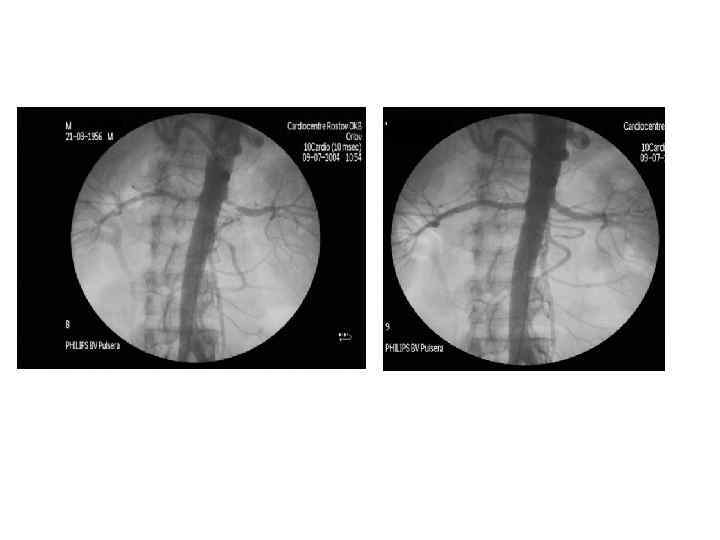

ИБП 1. РЕНОВАСКУЛЯРНАЯ АГ ЯВЛЯЕТСЯ ПРОЯВЛЕНИЕМ ИБП 2. В КАЧЕСТВЕ СКРИНИНГА – УЗТС ПОЧЕЧНЫХ АРЕТРИЙ С ДОПЛЕРОМЕТРИЕЙ И/ИЛИ КАПТОПРИЛОВЫЙ ТЕСТ 3. АНГИОГРАФИЯ ТОЛЬКО ПРИ РЕВАСКУЛЯРИЗАЦИИ 4. ПОМНИТЬ О ТОКСИЧНОСТИ КОНТРАСТОВ 5. НЕЛЬЗЯ ЛЕЧИТЬ БЛОКАТОРАМИ РААС 6. НАДО ОПЕРИРОВАТЬ 7. ЕСТЬ ГРУППА ЛИЦ, КОТОРЫМ ПРОВОДЯТ ИССЛЕДОВАНИЯ

ИБП 1. РЕНОВАСКУЛЯРНАЯ АГ ЯВЛЯЕТСЯ ПРОЯВЛЕНИЕМ ИБП 2. В КАЧЕСТВЕ СКРИНИНГА – УЗТС ПОЧЕЧНЫХ АРЕТРИЙ С ДОПЛЕРОМЕТРИЕЙ И/ИЛИ КАПТОПРИЛОВЫЙ ТЕСТ 3. АНГИОГРАФИЯ ТОЛЬКО ПРИ РЕВАСКУЛЯРИЗАЦИИ 4. ПОМНИТЬ О ТОКСИЧНОСТИ КОНТРАСТОВ 5. НЕЛЬЗЯ ЛЕЧИТЬ БЛОКАТОРАМИ РААС 6. НАДО ОПЕРИРОВАТЬ 7. ЕСТЬ ГРУППА ЛИЦ, КОТОРЫМ ПРОВОДЯТ ИССЛЕДОВАНИЯ

УЗТС почечной артерии (стеноз)

УЗТС почечной артерии (стеноз)